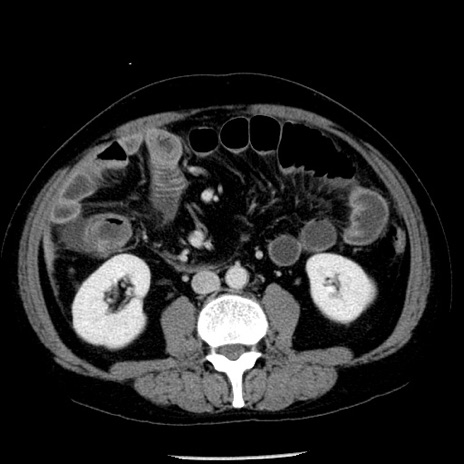

症例29(横断像)

【症例】40歳代男性

【現病歴】2日前から胃痛あり。徐々に周期的な激痛に変化した。本日になっても激痛があるため受診。

【身体所見】意識清明、BT 38-39℃台あり、腹部:膨満、やや硬、右下腹部に圧痛あり。

【データ】WBC 8500、CRP 23.26